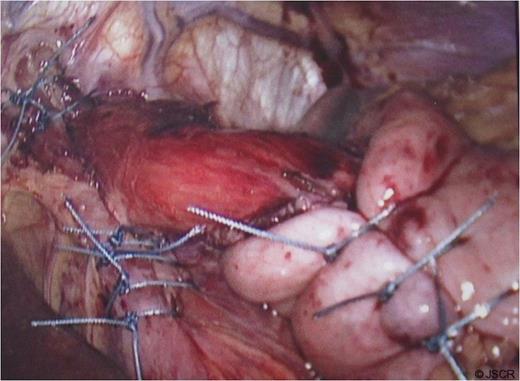

During the sac dissection, the patient developed tension pneumothorax due to an iatrogenic tear of the right pleura requiring a chest drain. He was closely observed in the high dependency unit with pain relief through PCA (morphine) and intravenous paracetamol and oral feeding commenced post-operatively. Arterial blood gas showed pO2 of 10.7 and PCO2 of 6.54 on 60% oxygen and an early post-operative chest x-ray revealed bilateral pulmonary infiltration (Fig. 3). Non-cardiogenic pulmonary oedema was suspected and the patient was started on 5mmHg pressure CPAP.

Early post-op chest x-ray showing patchy shadowing/ consolidation over the left side of chest